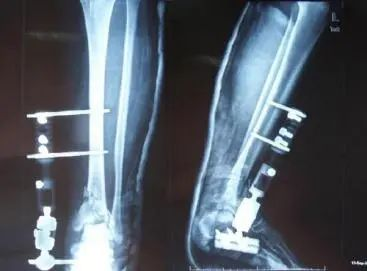

采用外固定支架结合有限内固定治疗则可避免上述治疗方法的并发症,一方面切开复位可使胫骨关节面尽量达到解剖复位,有限内固定可使复位后的骨折块保持一定的稳定性,同时采取撬拨复位克氏针或松质骨螺钉内固定(特别是闭合复位经皮固定),不需要广泛剥离软组织,减少了局部血供破坏的程度,使软组织得到有效的保护,降低皮肤坏死、内植物外露、感染等并发症的发生机率;另一方面外固定支架有牵引撑开的作用,非常有利于复位,可撑开和维持踝关节间隙,不仅减小了内固定针的负荷,而且防止关节囊及周围软组织的挛缩,还能通过肌腱关节囊的复位作用,使粉碎性骨折更好的复位,使关节间隙恢复正常,减轻关节压力,避免早期活动距骨对胫骨关节面的撞击,有利于后期关节面功能的恢复。同时外固定支架的万向布局特点可以调整旋转畸形,从而提高治疗效果,在治疗后期还可对骨折进行动力加压,促进骨折愈合。

1.有限内固定通过小切口固定主要骨折块,借助螺钉、骨片钉或克氏针有助于关节面的解剖复位与固定,有助于骨折端对位对线与稳定。

3.利用外固定支架独特的撑开作用,肌腱、韧带及软组织可使骨折更好的复位,即韧带整复术作用。

4.固定可靠,术后可早期扶拐下床活动,可于2-4周后定期放松远端万向关节,活动踝关节,从而有利于关节软骨的营养及关节模造作用,减少晚期创伤性关节炎的发生。

5.超关节功能为固定2-4周,有利于关节囊及韧带损伤的功能重建,防止晚期关节不稳。另外,对腓骨的固定在有效恢复肢体长度的同时亦能增强胫骨骨折端的稳定性,使患者早期下地成为可能。